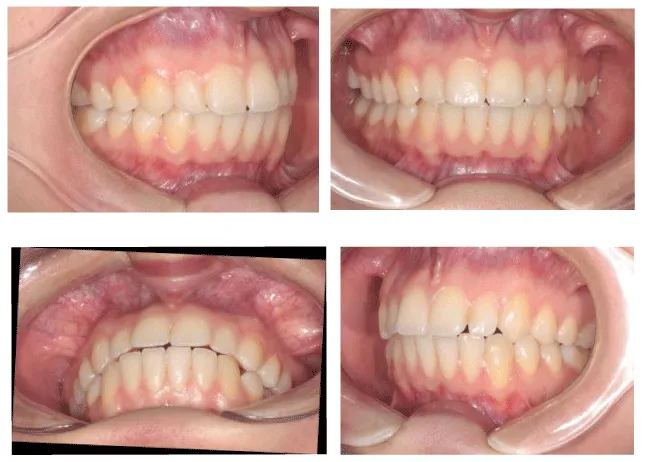

The procedure of the APTCA goes in the following sequence. After debanding patient is examined with T-scan III occlusal analysis procedure. The recording sequence is: centric occlusion, multi-bite, left lateral, and right lateral. Then occlusal foil (8 microns, Arti-Fol, Bausch, Germany) is placed between the teeth, patient is then asked to bite with the articulating paper in the mouth (Figure 2). Operator holds the articulating paper while the patient bites in his centric occlusion. These marks are then compared to the occlusal contacts viewed on the screen in patient`s centric occlusion recording (Figure 3). The highest forces on the teeth, which are seen on the screen exceeding the overall force level of 82%, have to be eliminated in the mouth. The force outliers on the screen are compared with paper marks on the patient`s teeth. The level of force does not usually correlate with the size of the occlusal mark. As described by Kerstein [20], small paper marks often tend to exhibit higher forces than larger marks.

After having eliminated extremely high forces marked in red and purple in centric occlusion, lateral excursions are analyzed. The purpose of lateral excursion recording is, first, to determine the time of disclusion (DT), and, secondly, to eliminate any contact on posterior maxillary and mandibular molars that prolongs the DT. One of these contacts, as shown in the case reports [10,11], is potentially prone to cause either buccal inclination of anterior teeth, or their rotation.

The APTCA procedure is implemented by disclusion time reduction, which was first described by Kerstein [19,21], in the region on posterior teeth, both maxillary and mandibular. First patient is asked to bite on the sensor in his centric occlusion and then slightly move to canine edge-to-edge contact (Figure 4). The recording is then analyzed and the DT is checked (Figure 5). DT should not exceed 0,5 seconds [20]. Then the patient is asked to occlude his teeth in centric occlusion with green occlusal paper between his teeth. The excursive movement is afterwards performed with the use of red occlusal paper to mark excursive contacts. The method implements two colors of occlusal paper to mark centric occlusal contacts in green and excursive contacts in red. Red marks are easily recognizable and can be removed according to canine guidance scheme. The aim of APTCA is to achieve pure canine guidance in 0,5 seconds, eliminating posterior excursive contacts primarily. These contacts are consequently removed after each recording. The patient performs excursive movement with a sensor, paper marks are checked in the mouth, then excursive contacts removed on posterior teeth, and again the patient is asked to bite the sensor. It may take up to 8-10 cycles of repeated adjustment to achieve proper DT on the working side. The same procedure is done on the opposite side, when the patient performs lateral movement on the opposite working side.